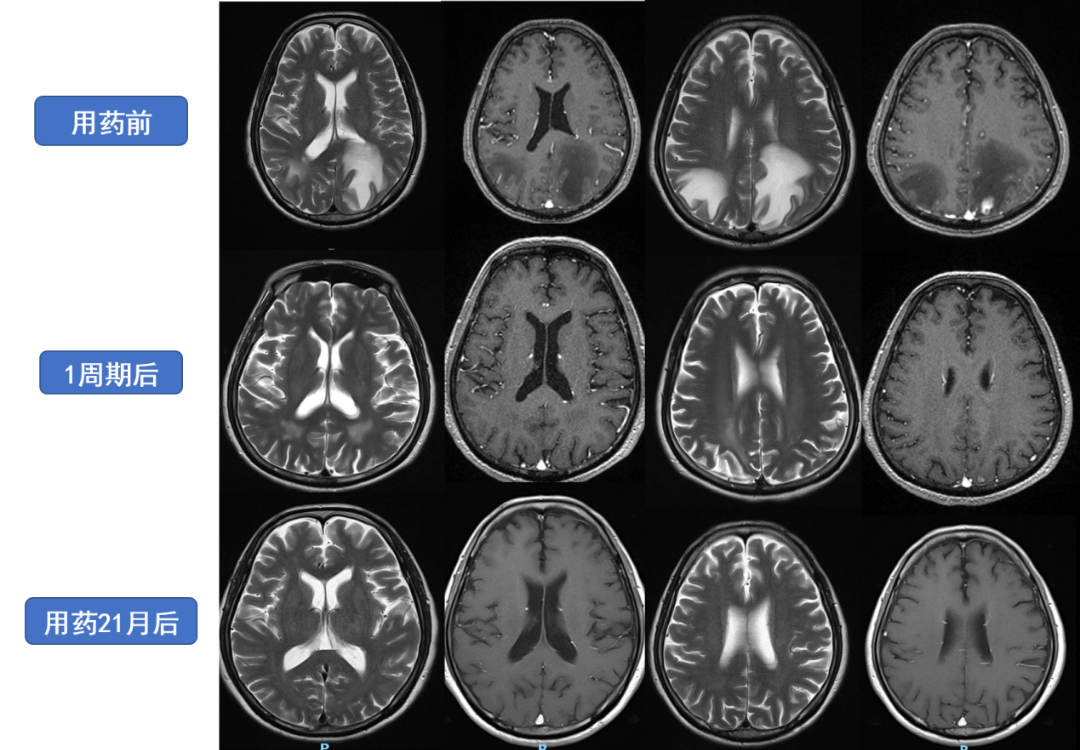

图1治疗期间颅内病灶动态变化

经过治疗,患者的颅内病灶基本达到了临床完全缓解,同时胸壁的转移灶消失,整体疗效评估为部分缓解(PR)。对于MET扩增的患者,及时采用MET抑制剂进行针对性治疗,能够更好地控制疾病进展,取得更好的治疗效果。临床研究表明伯瑞替尼对MET 14跳跃突变、MET扩增的NSCLC具有不错的疗效,表现在起效迅速,肿瘤退缩明显,疗效持久。同时在安全性方面,伯瑞替尼的不良反应大部分为1-2级,整体可控,期待该药物早日可及惠及更多临床患者。